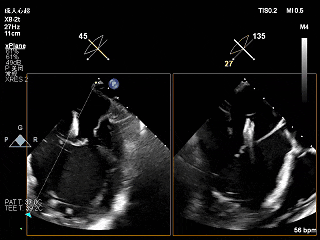

夹子关小后3D观察组织桥

夹子关小后3D上彩

反流降至轻度

夹子释放后,2D下color,反流降至轻度

夹子释放后3D下观察组织桥稳定,反流降至trace

夹子释放后压差为2mmHg

肺静脉逆流明显改善